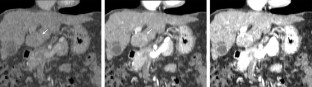

Fig. 4